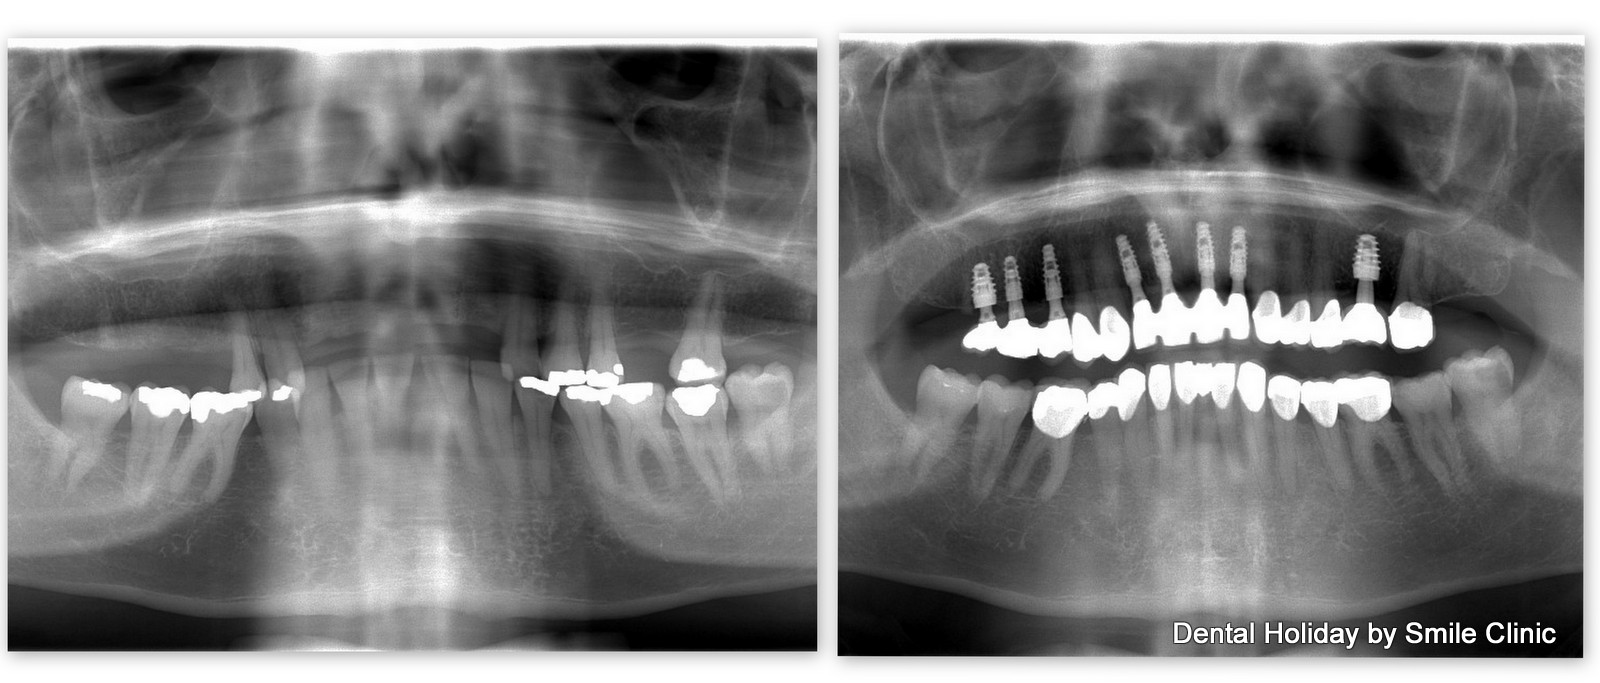

As you can see from the x-ray, Brian had just a handful of loose teeth left in his upper jaw.

For the lower jaw, we placed 12 crowns to add strength to the bite of the newly completed upper jaw. This should help the existing natural teeth in the lower jaw to last much longer (if left alone, they would have become loose over time just as with the top teeth before).